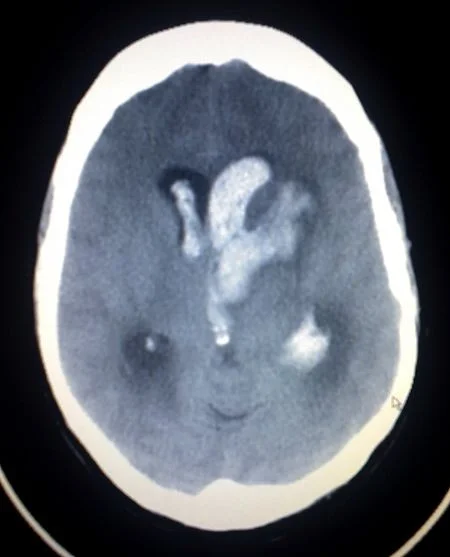

Intracranial hematoma:

Is a collection of blood within the skull, most commonly caused by rupture of a blood vessel within the brain or from trauma. There are four types:

Subarachnoid Hemorrhage: SAH

Is bleeding into the subarachnoid space the area between the arachnoid membrane and the pia mater surrounding the brain. Traumatic SAH: Blow to lateral neck with resulting damage to Vertebral Artery. Signs and symptoms:

Intracerebral Hemorrhage

Is when blood suddenly bursts into brain tissue, causing damage to the brain.